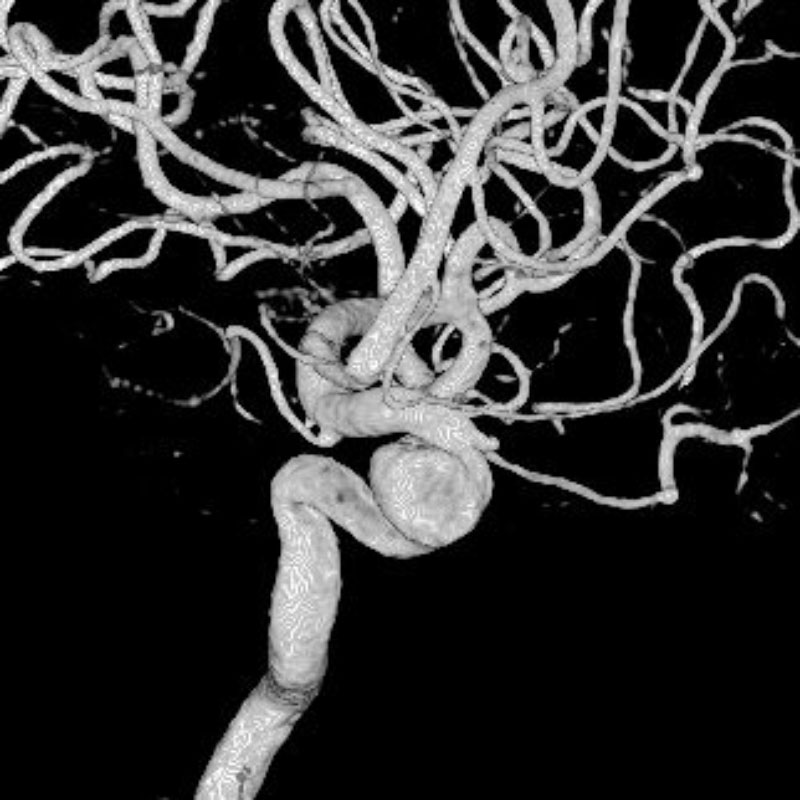

脳動静脈奇形

血管塞栓術

松田/濵田/元永